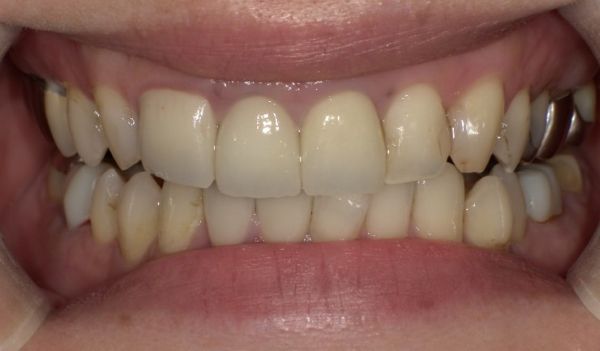

特に処置後も痛みなどはなく、状態も安定しています。色調にもご満足いただけました。

今回の症例では、前歯の色調に対する不満、過去に治療するか迷っていた歯に関する将来的な不安から、やり替え治療と新たな被せ物治療のご希望がありました。

今回の被せ物に関しては、セラミックでの治療なので、金属を使用していないため、歯と歯茎の境目に金属色が見えてくるなどのリスクもありません。セラミックの中でも、ジルコニアセラミックを使用することで色調だけでなく、汚れがつきにくく、強度もあり、長期的に使用可能な被せ物を装着することができます。また、ご自身の歯との色の違いを最小限にするように心がけました。